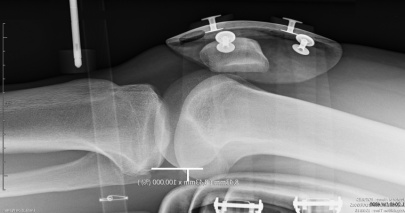

RADIOLOGIE

Die automatisierte dynamische Laximetrie für einen neuen Ansatz in der Untersuchung der Funktion der Bänder

Die LDA® erlaubt die Messung und Berechnung neuer Werte um eine hochkomplexe radiologische Untersuchung der Funktion der Kniebänder zu ermöglichen.

Der LDA® Test ist eine unverzichtbare Ergänzung der medizinischen Bildgebung in der Untersuchung des VKB's. Er erlaubt eine dynamische Vorstellung durch die Erfassung der Widerstandskurven der Bänder.

Das GNRB Radio ist speziell gestaltet für einen rationellen Einsatz in der Radiologischen Praxis

Der LDA © Test ist einfach, schnell und komfortabel für den Patienten (liegend auf der Radiologie Tisch). Er ist innerhalb von Minuten während der radiologischen Untersuchung durchführbar.

Das GNRB Radio besitzt eine 5 sekündige Sperrfunktion für die Translation in der oberen Position, um Röntgenbilder zu erfassen.

Eine patentierte Messmethode

Der Lachmann Test ist mit dem GNRB Radio vollständig automatisiert

Die Werte der Fixation von Knöchel und Oberschenkel werden gespeichert. Die LDA® Software synthetisiert und vergleicht sofort die an beiden Knien vorgenommenen Messungen, durch die Vermessung der Steigungen der Widerstands-Kurven der VKBs (Innovation Genourob)

Gezeigtes Beispiel : Präoperative Kontrolle

Δ 134 = 6 mm, Δ P2 = 2

Komplette Ruptur

Objektivierung eines klinischen Lachmann-Tests